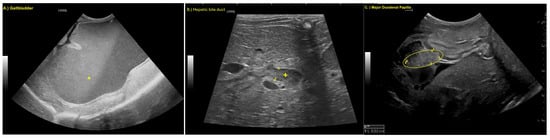

Findings were overall unchanged to mildly progressive, with the additional observation of a thickened major duodenal papilla (Figure 2).

Figure 2. (A) Marked dilation of the gallbladder (*), (B) dilated hepatic bile duct, (+, boarders marked with 1 and +) and (C) thickened major duodenal papilla (oval, boarders of papilla marked with +, 1 and 2).